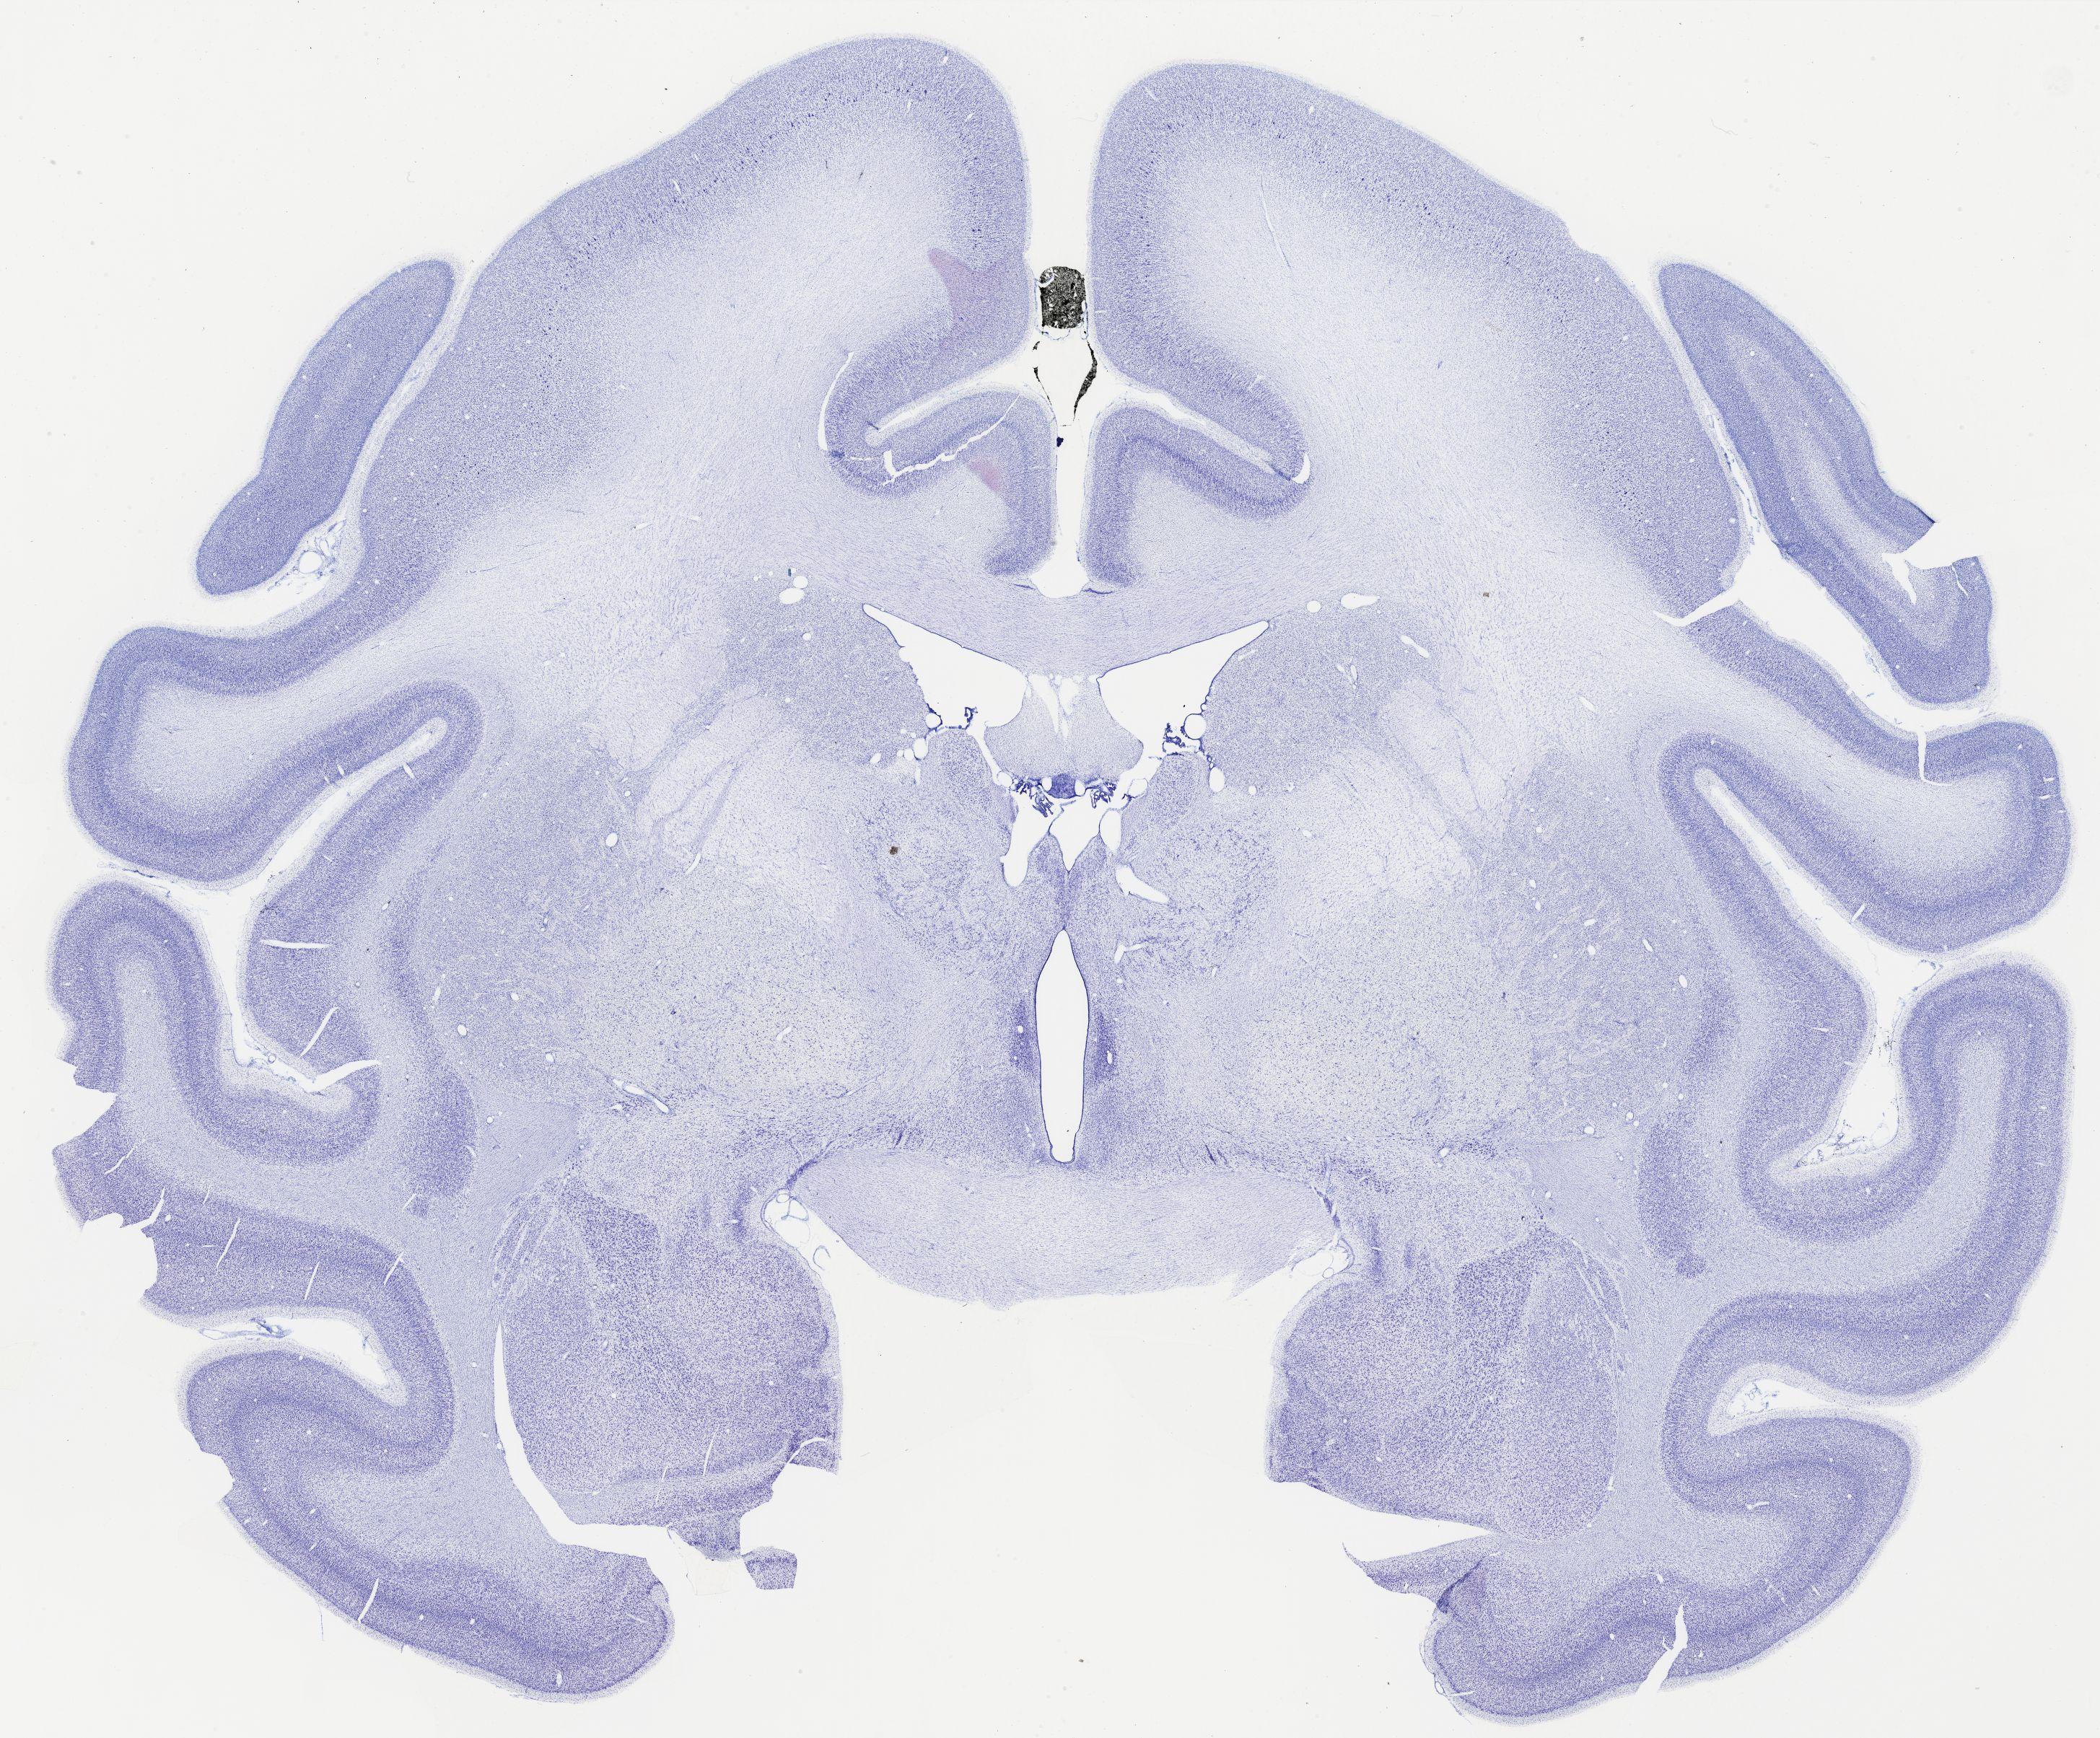

thumbnail

323